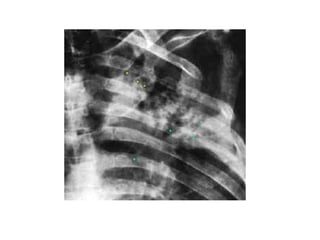

BRONCOGRAMA AEREO

BRONCOGRAMA AÉREO: